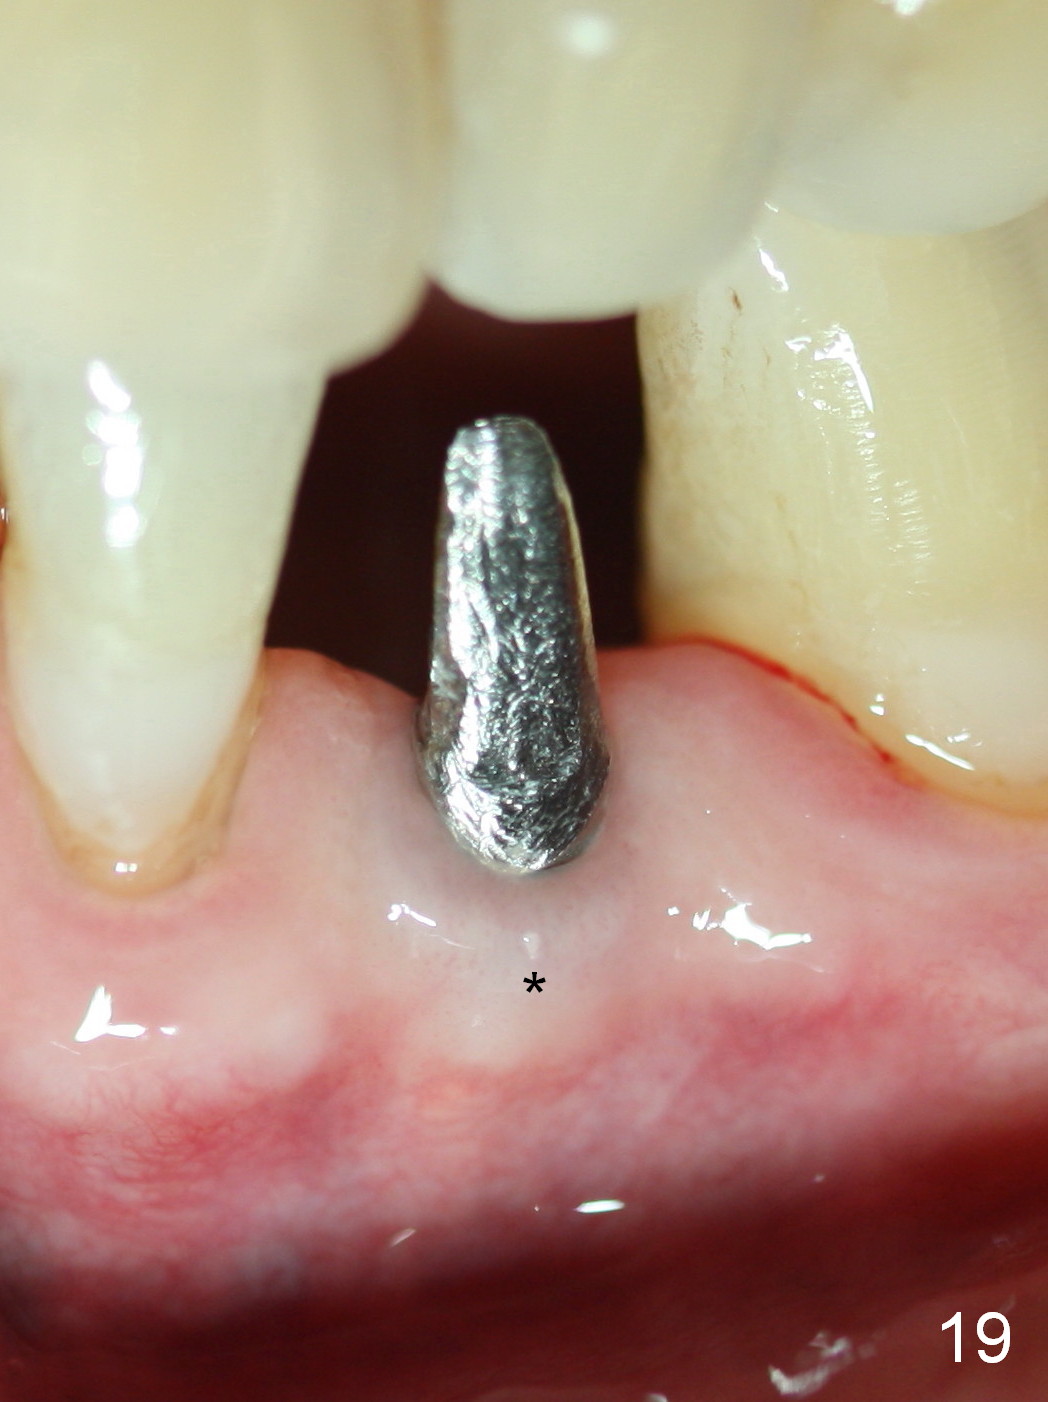

Five months postop, the peri-implant space reduces (Fig.18). A keratinized band forms buccal to the implant (Fig.19 *). The provisional dislodges probably due to the buccal placement (Fig.20).